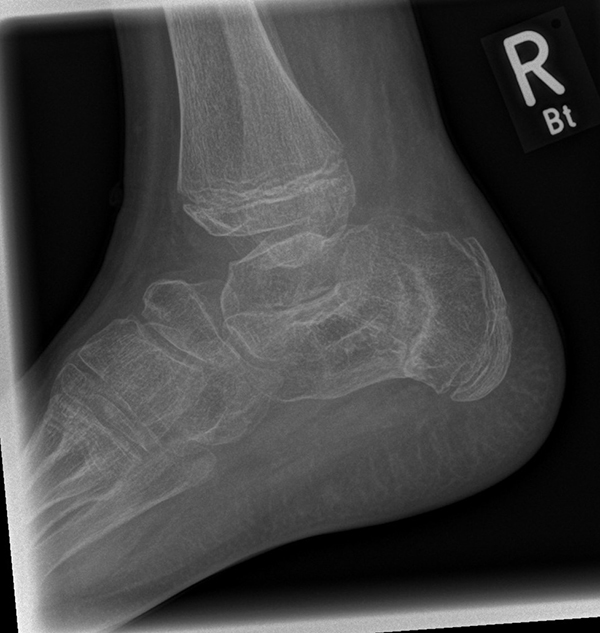

Knick-Senk-Platt-Fuß Korrektur mit dem Canalis Tarsi Spacer

In der Korrektur des schmerzhaften, aber flexiblen Knick-Senk-Fußes oder Plattfußes ist die Schraubenarthrorise mit einem Sinus tarsi oder besser bezeichnet als Canalis tarsi Spacer und alternativ mit einer Calcaneus-Stopp-Schraube seit vielen Jahren ein etabliertes Verfahren und führt zu einer kompletten Korrektur von flexiblen Knick- und Plattfuß-Fehlstellungen (Abb. 7). Die nötige Schnittlänge über dem Sinus tarsi beträgt für beide Verfahren 1 cm.

Abb. 7 a-e: Knick-Senk-Fuß prä- und postoperative Situation (a-b), ventrale und dorsale Ansicht (c-d). Laterale Ansicht des Hautschnittes über dem Sinus tarsi (e).